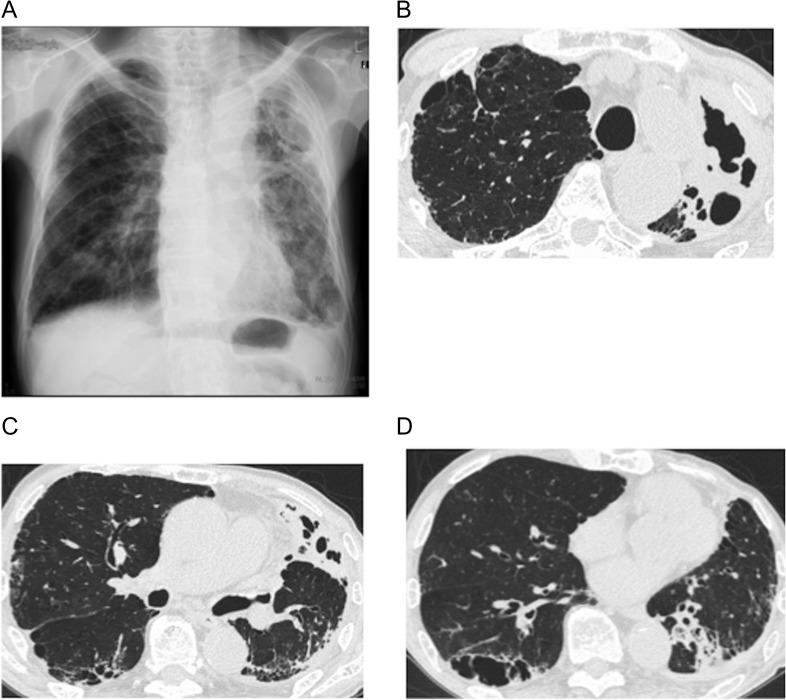

An 84-year-old man visited our hospital with a prolonged productive cough. Chest computed tomography showed a thick wall cavity and bilateral consolidations. Laboratory findings revealed peripheral blood eosinophilia, increased total IgE and elevated myeloperoxidase anti-neutrophil cytoplasmic antibody. Specific IgE and IgG antibodies and an immediate skin reaction against showed positive results. The histological findings of the lung parenchyma were compatible with eosinophilic pneumonia and bronchial biopsy showed eosinophilic vasculitis. Bronchoalveolar lavage fluid culture yielded . These results met the diagnosis criteria for both allergic bronchopulmonary aspergillosis (ABPA) and eosinophilic granulomatosis with polyangiitis (EGPA). This case thus suggests that might be a pathogen common to both diseases, and prolonged exposure to in some patients with ABPA may promote progression to EGPA.

一名84岁男性因长期咳痰前来我院就诊。胸部计算机断层扫描显示有厚壁空洞和双侧实变。实验室检查结果显示外周血嗜酸性粒细胞增多、总IgE升高以及髓过氧化物酶抗中性粒细胞胞浆抗体升高。针对特定物质的特异性IgE和IgG抗体以及即刻皮肤反应呈阳性结果。肺实质的组织学检查结果符合嗜酸性粒细胞性肺炎,支气管活检显示嗜酸性血管炎。支气管肺泡灌洗 fluid culture yielded(此处原文有误,无法准确翻译)。这些结果符合变应性支气管肺曲霉病(ABPA)和嗜酸性肉芽肿性多血管炎(EGPA)的诊断标准。因此,该病例提示某种物质(此处原文有误,无法准确翻译)可能是这两种疾病的共同病原体,并且在一些ABPA患者中长时间接触该物质可能会促进疾病进展为EGPA。